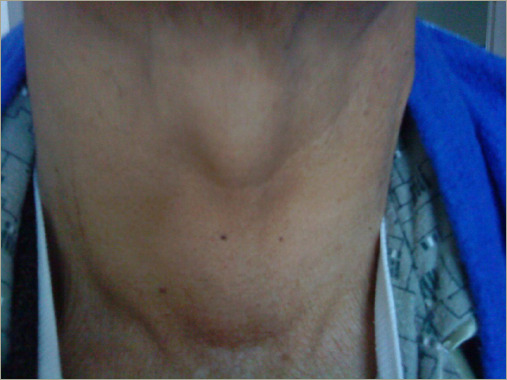

Introduction: Amyloid goiter (AG) is a rare cause of thyroid swelling, characterized by deposits of amyloid protein in the thyroid tissue. It can be associated with primary or secondary amyloidosis. Its prevalence in multinodular goiter cases is 0.17%, with rare clinical detection before surgery. Case series: This Peruvian case series comprised three female patients and one male patient, with ages ranging from 28 to 65 years. All individuals had pre-existing inflammatory diseases and reported symptoms including dyspnoea, dysphagia and dysphonia. Upon physical examination, all patients exhibited a grade III goiter. Fine-needle aspiration reported colloid goiter. Three out of the four patients underwent total thyroidectomy and histochemistry revealed AG with positive Congo red staining. Discussion: AG is an uncommon clinical entity. It has been reported to occur more frequently in males, with an average age of diagnosis of 40 years. In our series, we observed a broad age range of patients receiving diagnoses, spanning from 28 to 65 years, with a predominance in females. The consideration of AG should be extended to every patient with an underlying chronic systemic inflammatory disease, especially end stage renal disease. In this context, AG should be included in the differential diagnosis for patients with multinodular goiter exhibiting progressive growth and causing compressive symptoms at the cervical level without affecting thyroid function, as demonstrated in our series. Conclusion: AG, a rare condition, warrants suspicion in the presence of a giant goiter with an underlying systemic inflammatory disease.